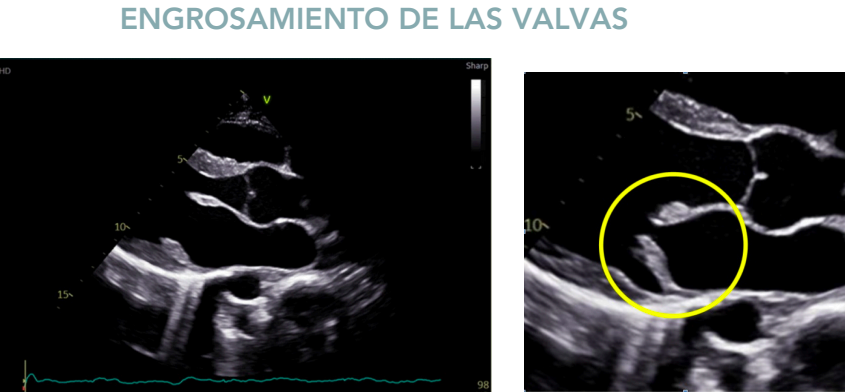

Hallazgos ecocardiográficos

- Regurgitación mitral (Doppler color).

- Engrosamiento y prolapso valvular.

- Dilatación de AI y VI.

- Hipertrofia excéntrica del VI.

- Alteración del flujo mitral (ondas E y A).

Regurgitación mitral:

Engrosamiento de las valvulas